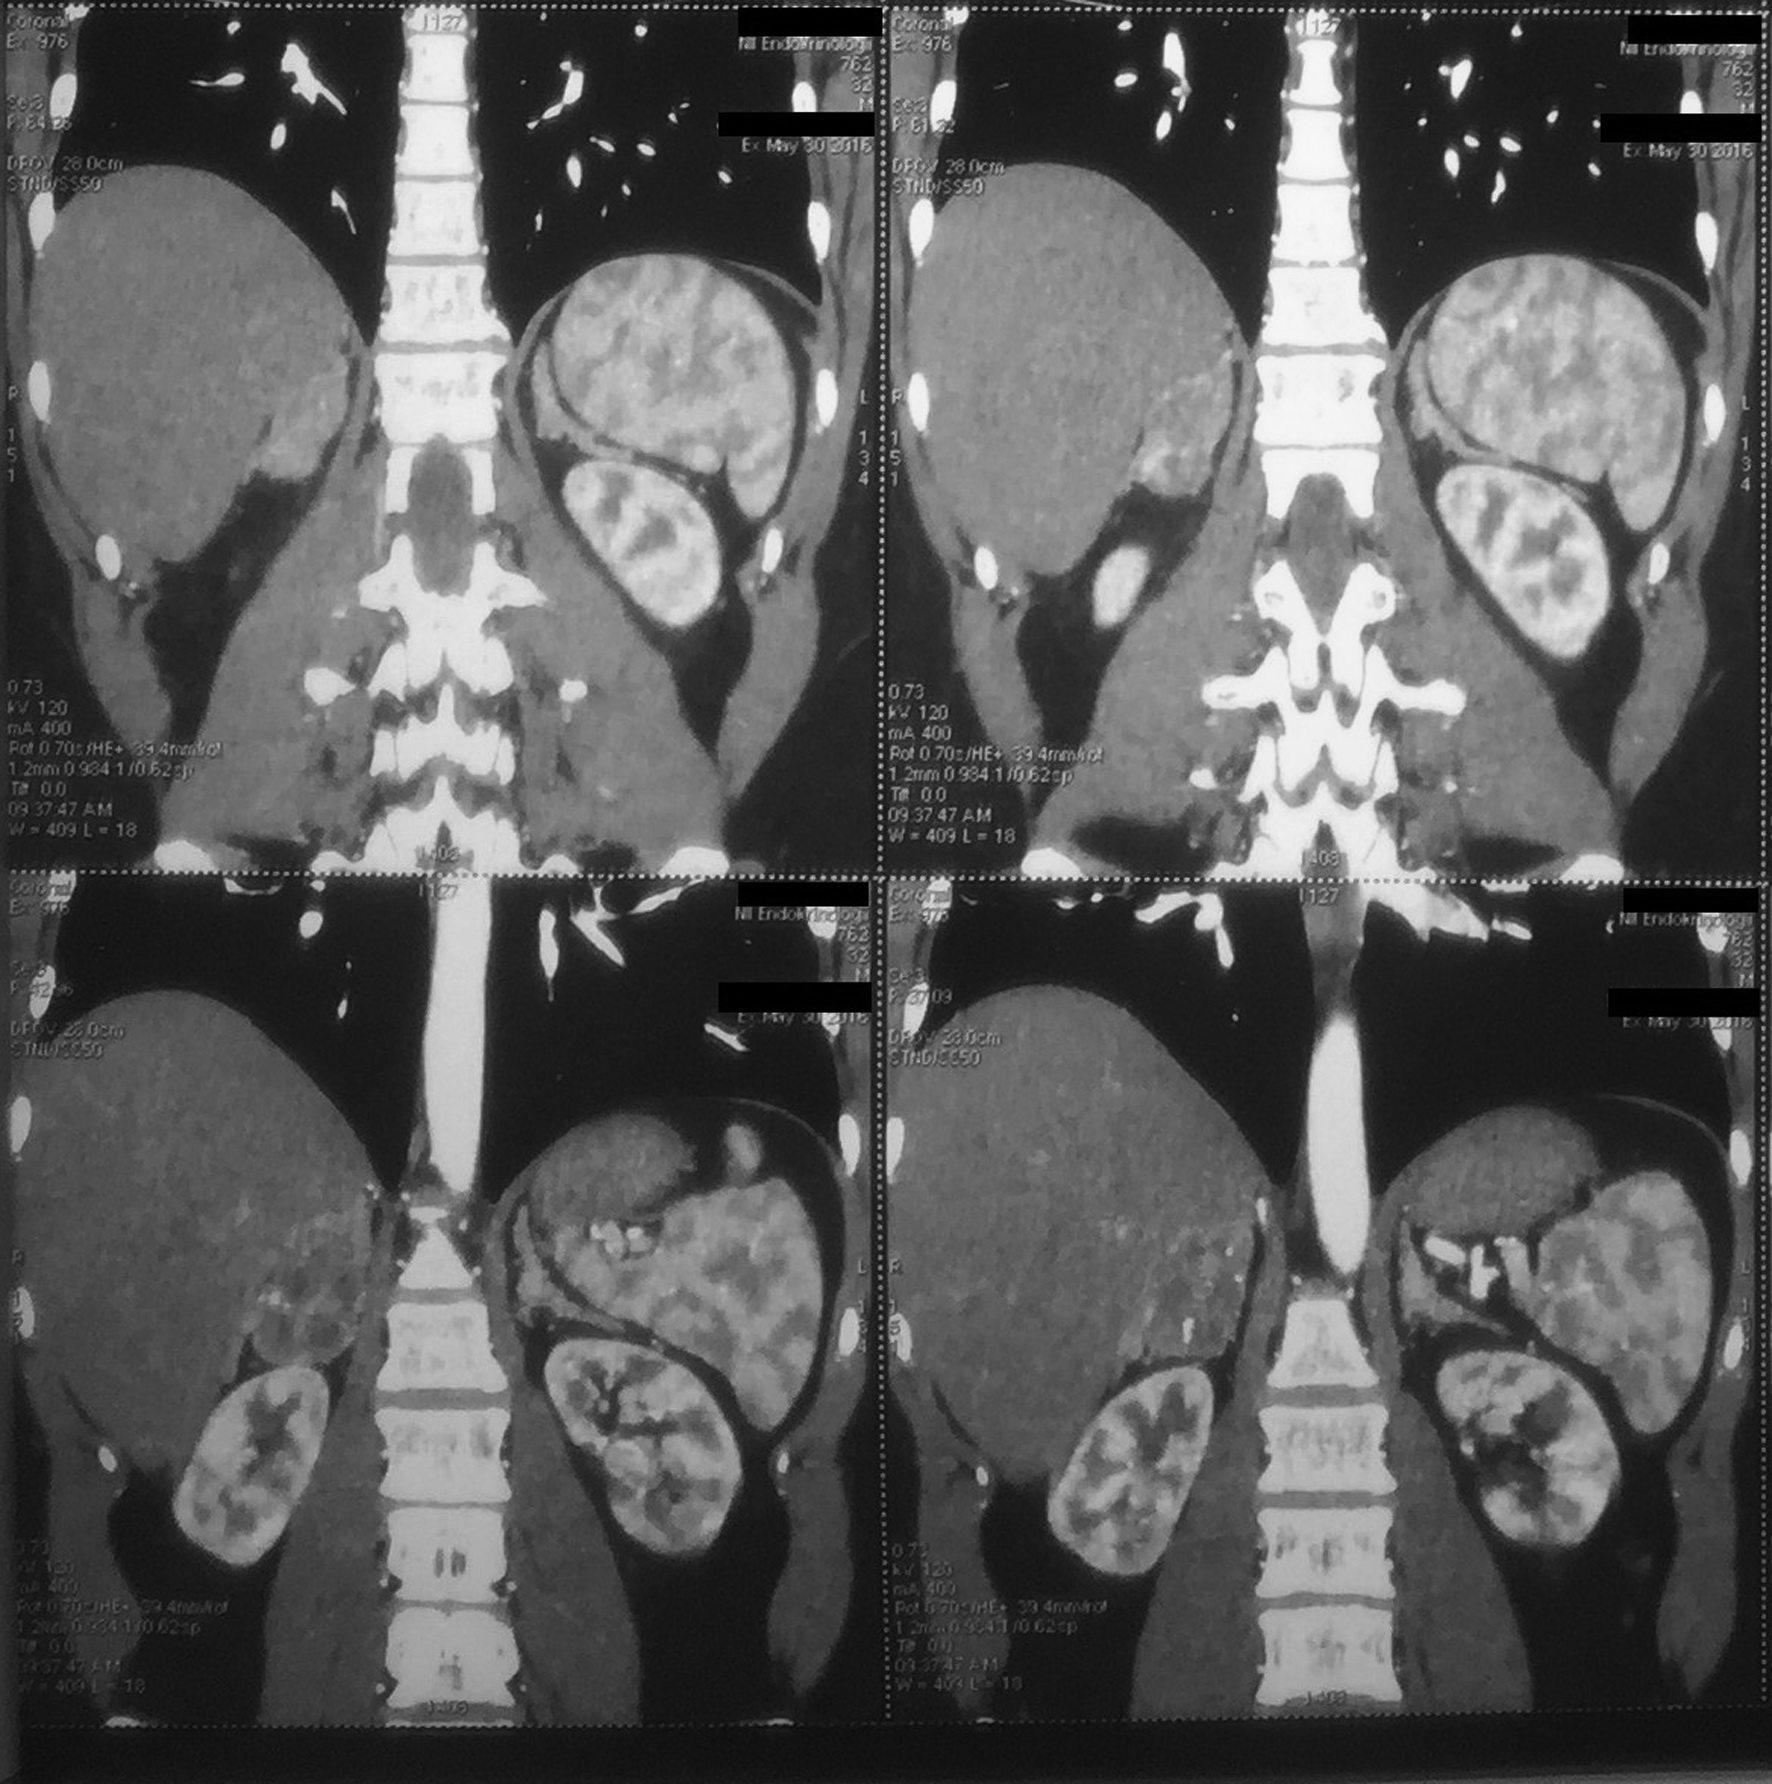

При МРТ головного мозга данных за патологию, в том числе гипофиза, не получено. При МСКТ брюшной полости у пациента была выявлена аденома правого надпочечника размером 48×35×43 мм на фоне двустороннего утолщения надпочечников (рис. 2).

Рис. 2. МСКТ брюшной полости пациента О.

Определяется аденома правого надпочечника, двустороннее утолщение надпочечников.

Длительная декомпенсация ВДКН, сопровождающаяся значительным повышением уровня АКТГ, объясняет развитие двусторонней гиперплазии надпочечников и аденомы правого надпочечника. В связи с высоким уровнем андрогенов адреналового происхождения у пациента развился гипогонадотропный гипогонадизм, сопровождающийся гипоплазией яичек, азооспермией.

Одним из частых осложнений при поздней диагностике ВДКН или его длительной недостаточной компенсации являются вторичные образования в надпочечниках [9, 10], которые были выявлены и у нашего пациента. Так как появление аденом связано с длительной массивной гиперстимуляцией надпочечников АКТГ, то в большинстве случаев они подвергаются регрессии на фоне адекватной стероидной терапии. Хирургическое лечение применяется в исключительных случаях, при появлении признаков функциональной автономии образования. В нашем случае значительное снижение АА и 17-ОПГ на фоне терапии указывало на хорошую чувствительность аденом к стероидам.